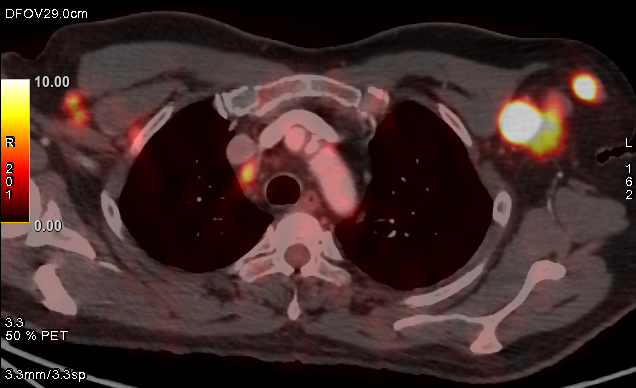

PET/CT:

Oncology

FDG PETCT whole body scan for cancer staging, restaging, response assessment, follow-up and guided biopsy

FDG PETCT